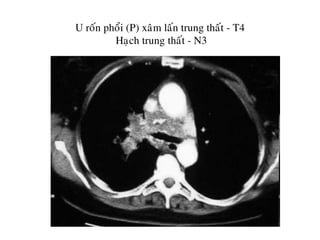

U roán phoåi (T). T4. Xeïp phoåi phía xa

Haïch döôùi carina

Haïch trung thaát hai beân, tröôùc khí quaûn -N3

U roán phoåi (P) xaâm laán trung thaát - T4

Haïch trung thaát - N3